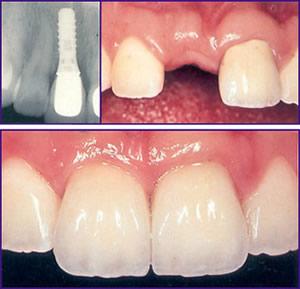

* Implanturi dentare; * Lifting de sinus maxilar; * Grefa osoasa si aditie biomateriale cu propietati regenerative; * Interventii chirurgicale parodontale cu lambou; * Chiuretaje radiculare; * Chirurgia plastica a rozului gingival (gingivectomie, gingivoalveoloplastie); * Extractii dentare plastice; * Chirurgia periradiculara (rezectie apicala, amputatii radiculare).